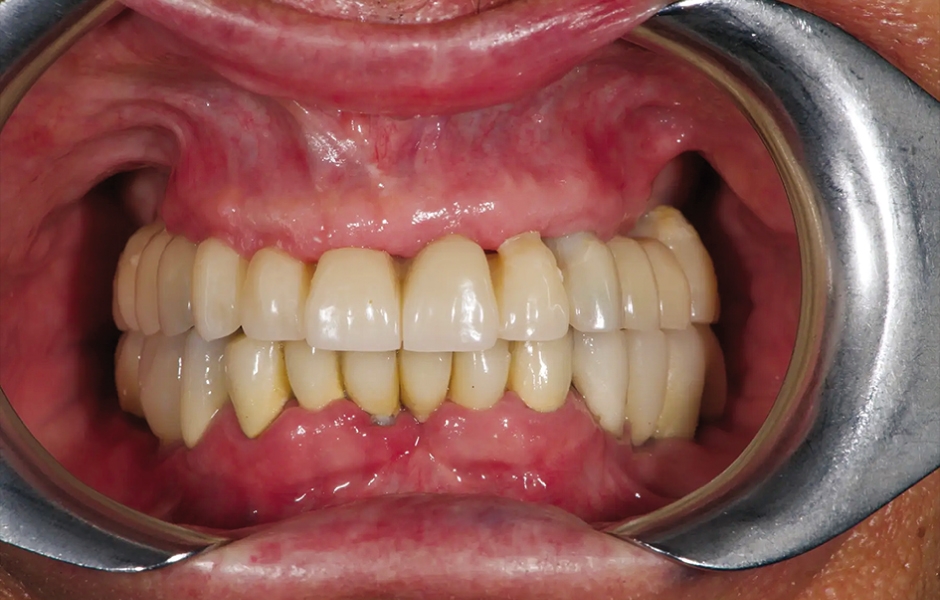

85letý částečně bezzubý pacient byl odeslán na naši kliniku k celkové rehabilitaci horní čelisti. Pacient byl v dobrém celkovém zdravotním stavu a nekuřák. Jeho hlavní stížnosti zahrnovaly obtíže při žvýkání, bolest v horní čelisti a občasný zápach z úst. Klinické a radiologické vyšetření odhalilo krátký fixní metalokeramický můstek nesený sedmi frontálními zuby horní čelisti. Protetická práce se uvolnila a čtyři z pilířových zubů byly strukturálně narušeny. Zbývající tři vykazovaly různé stupně kazivých lézí a parodontálních problémů. Byla stanovena diagnóza selhávající dentice (obr. 1 a 2).

Obr. 1: Výchozí situace, čelní pohled. (Všechny snímky: Dr. Marco Tallarico a kol.).

Obr. 2: Výchozí situace, okluzální pohled.